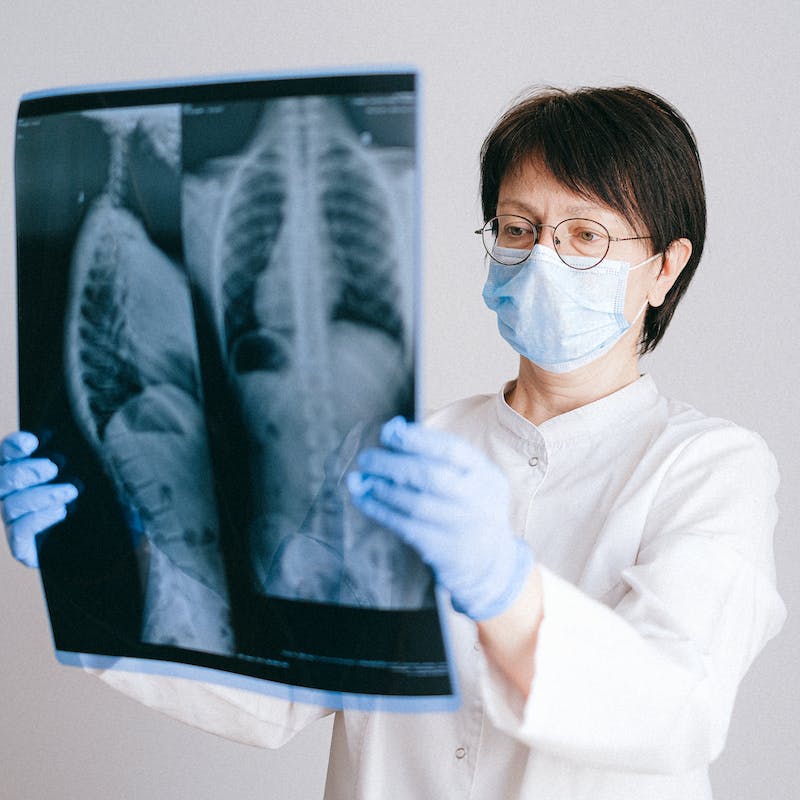

Radiografía de Tórax

Ideal para el diagnóstico de condiciones que afectan a la pared torácica y/o órganos alojados en el tórax. Una de las pruebas imagenológicas más usadas.